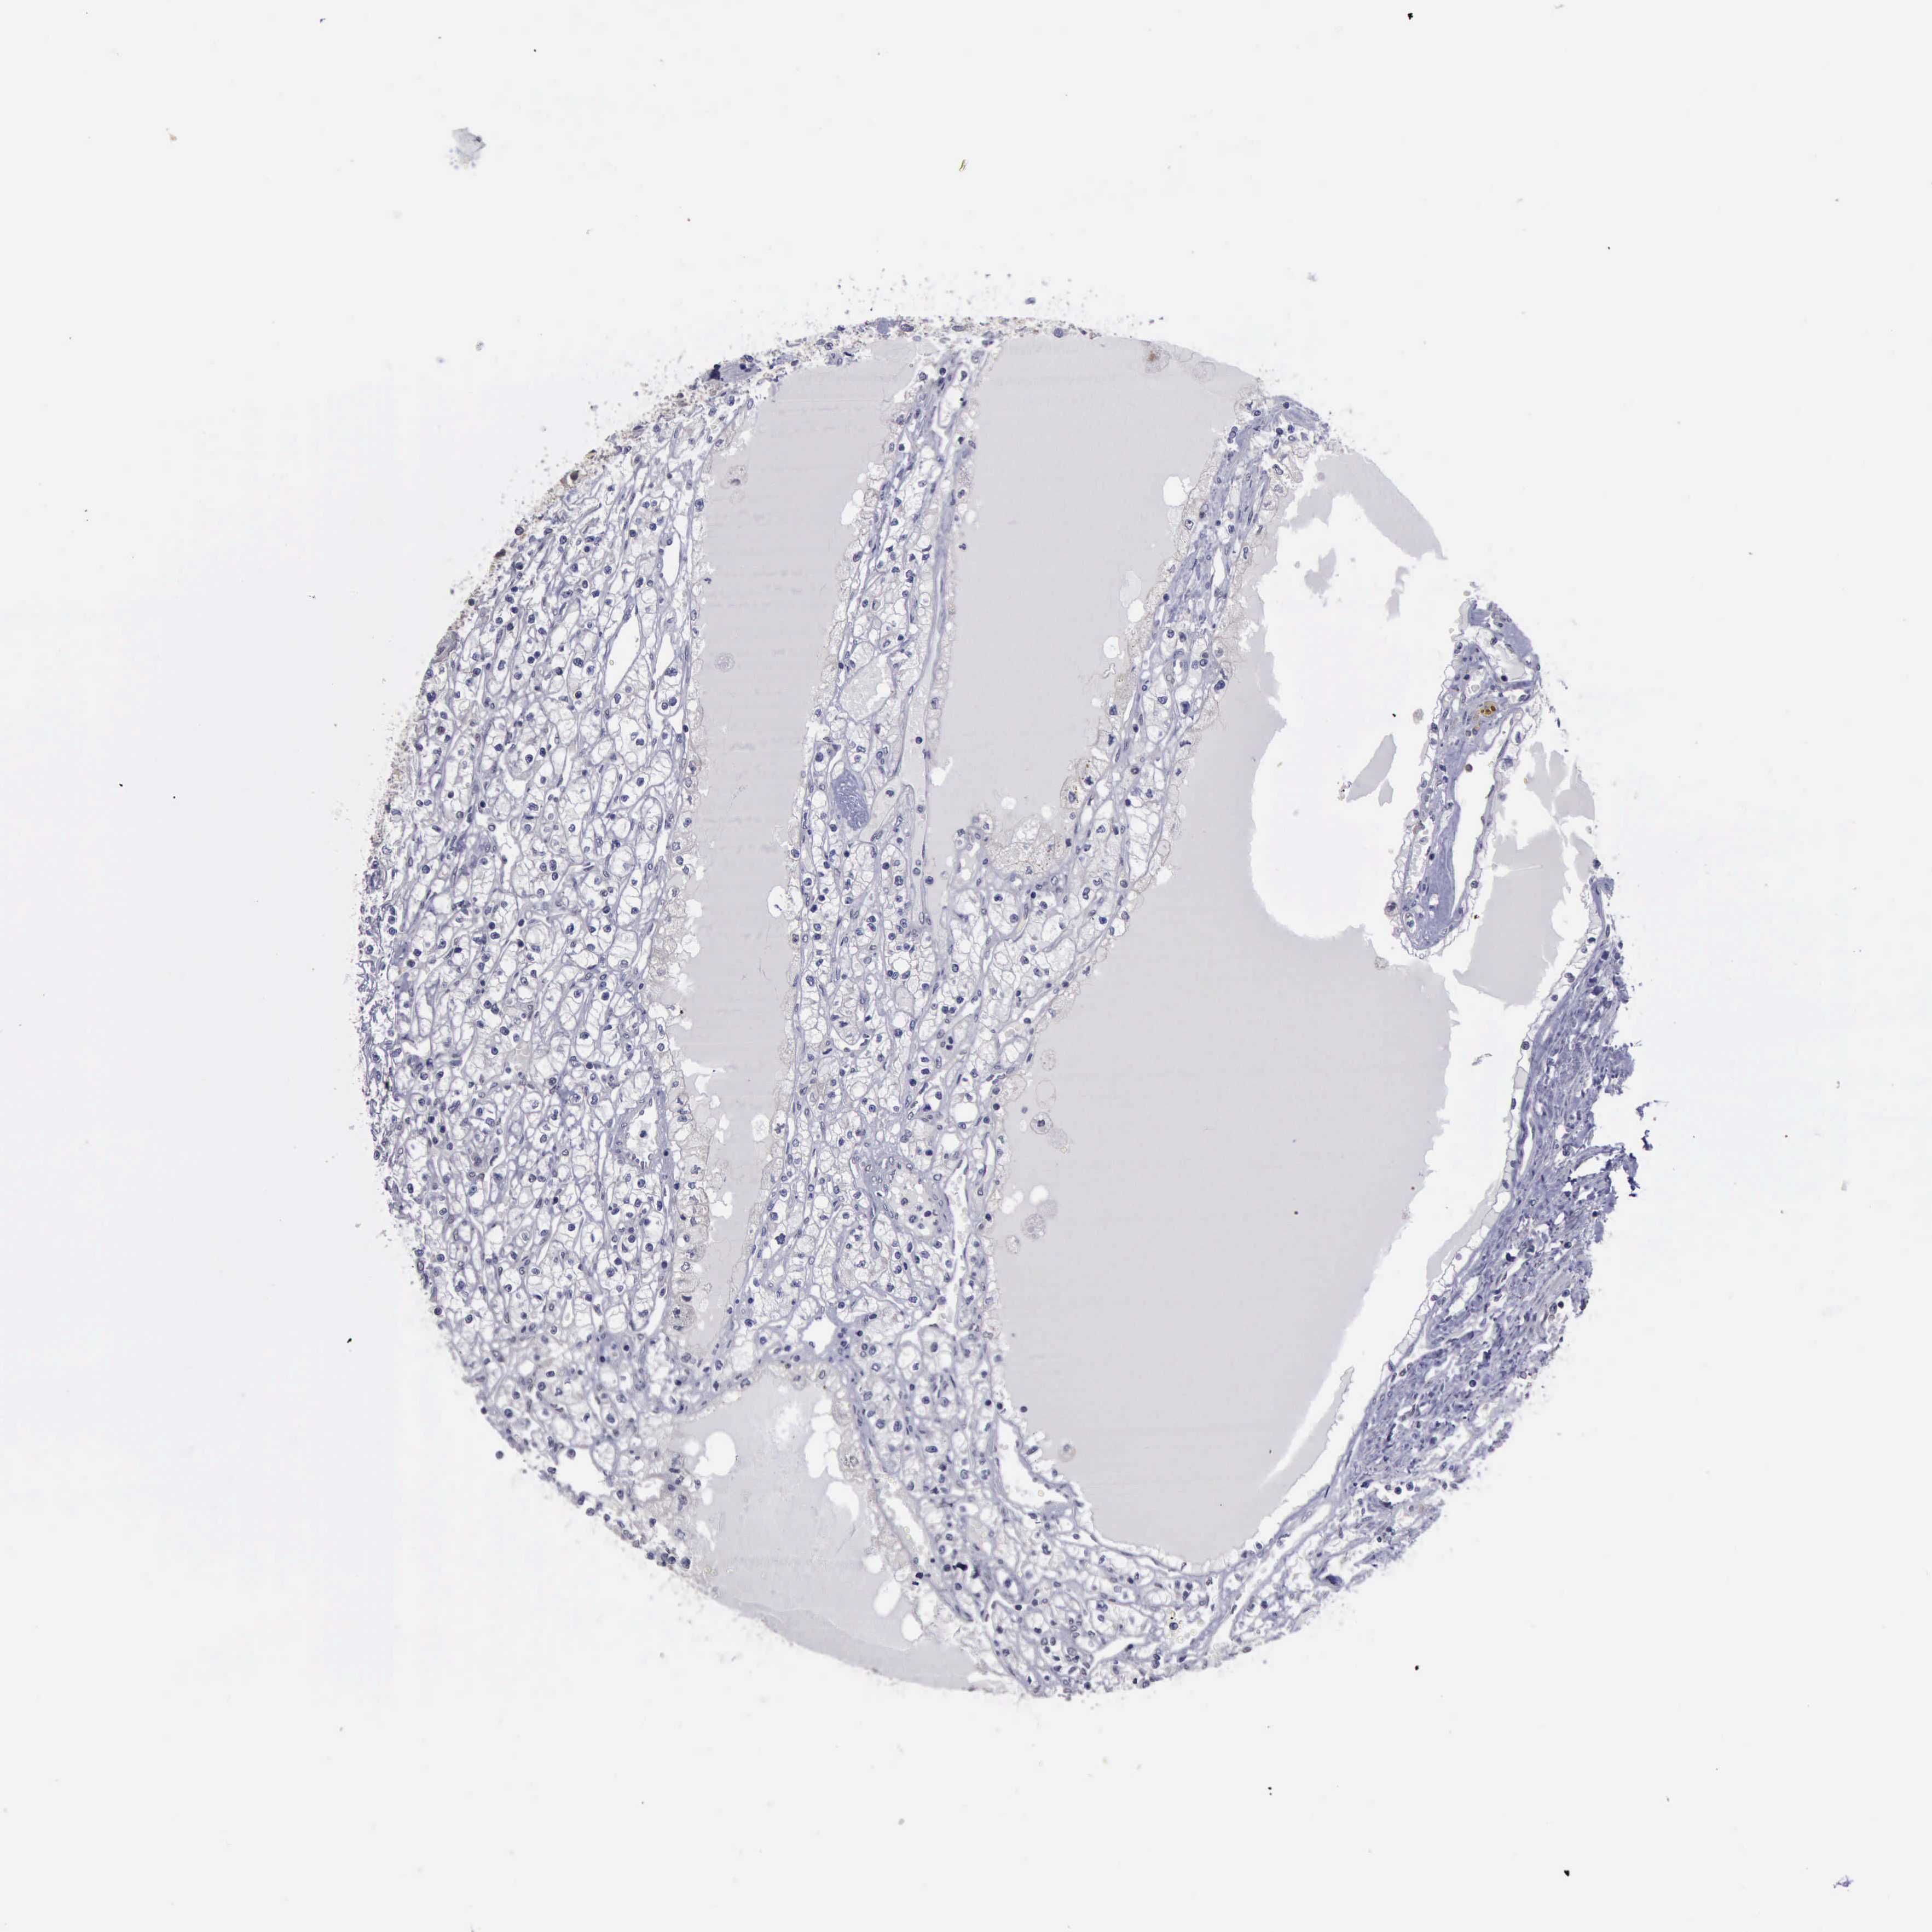

KIDNEY RENAL CLEAR CELL CARCINOMA (VALIDATION) - Interactive survival scatter ploti

The Survival Scatter plot shows the clinical status (i.e. dead or alive) for all individuals in the patient cohort, based on the same data that underlies the corresponding Kaplan-Meier plots. Patients that are alive at last time for follow-up are shown in blue and patients who have died during the study are shown in red.

The x-axis shows the expression levels (FPKM) of the investigated gene in the tumor tissue at the time of diagnosis. The y-axis shows the follow-up time after diagnosis (years). Both axes are complimented with kernel density curves demonstrating the data density over the axes. The top density plot shows the expression levels (FPKM) distribution among dead (red) and alive patients (blue). The right density plot shows the data density of the survived years of dead patients with high and low expression levels respectively, stratified using the cutoff indicated by the vertical dashed line through the Survival Scatter plot. This cutoff is automatically defined based on the FPKM cutoff that minimizes the p-score. The cutoff can be changed by dragging the vertical line or by entering a cutoff value in the square labeled "Current cut-off".

Under the Survival Scatter plot the p-score landscape (black curve; left axis) is shown together with dead median separation (red curve; right axis). Dead median separation is the difference in median mRNA expression between patients who have died with high and low expression, respectively. It is calculated as follows: median FPKM expression of dead patients with high expression - median FPKM expression of dead patients with low expression. This is intended to aid the user in visually exploring custom cutoffs and the associated p-scores and dead median separation.

Individual patient data is displayed and can be filtered by clicking on one or more of the category buttons on the top of the page. Categories describing expression level and patient information include: high, low, alive, dead, female, male and tumor stages. The scale of the x-axis can be toggled between linear and log-scale by clicking on the "x log" button. Mouse-over function shows TCGA ID, patient information and mRNA expression (FPKM) for each patient.

& Survival analysisi

Kaplan-Meier plots summarize results from analysis of correlation between mRNA expression level and patient survival. Patients were divided based on level of expression into one of the two groups "low" (under cut off) or "high" (over cut off). X-axis shows time for survival (years) and y-axis shows the probability of survival, where 1.0 corresponds to 100 percent.

PHKA1 is not prognostic in Kidney Renal Clear Cell Carcinoma (validation)

Best expression cut offi

Based on the FPKM value of each gene, patients were classified into two groups and association between prognosis (survival) and gene expression (FPKM) was examined. The best expression cut-off refers the FPKM value that yields maximal difference with regard to survival between the two groups at the lowest log-rank P-value. Best expression cut-off was selected based on survival analysis .

When clicking on this number, the vertical dashed line indicating cut-off, the interactive survival plot, and the Kaplan-Meier curve will be adjusted to show results based on the best expression cut-off.

: 2.96

TCGA RNA samplesi

RNA-seq data is reported as average FPKM (number Fragments Per Kilobase of exon per Million reads), generated by the The Cancer Genome Atlas (TCGA) .

Normal distribution across the dataset is visualized with box plots, shown as median and 25th and 75th percentiles. Points are displayed as outliers if they are above or below 1.5 times the interquartile range. FPKM values of the individual samples are presented next to the box plot.

Average pTPM 6.6

Number of samples 100